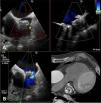

We present the case of an 85-year-old male patient with a history of digestive hemorrhage with hypovolemic shock and hemorrhagic stroke with ad integrum restitution. He had permanent atrial fibrillation (CHA2DS1-VASc: 6 and HAS-BLED: 5) and was receiving indefinite oral anticoagulation with Apixaban®. After the last episode of bleeding, the patient was referred for left atrial appendage closure and underwent a successful 24 mm Watchman device implantation (Boston Scientific, MN, USA), with the presence of a small leak <3 mm that was managed conservatively. Two years after the implant, he suffered a new episode of ischemic stroke in the frontal lobe. Transesophageal echocardiography (TEE) revealed the presence of two significant leaks >5 mm, one on the posterosuperior side and the other on the anteroinferior side (Figure 1, Video 1-2). Due to high hemorrhagic risk, the patient underwent percutaneous closure of the leaks.

A: Transesophageal echocardiography (TEE) image showing anteroinferior leak (yellow arrow) and posterosuperior leak (white arrow). B: Transesophageal echocardiography with TEE image showing color flow Doppler through the posterosuperior leak. C: Computed tomography image showing leaks on both sides of the device.